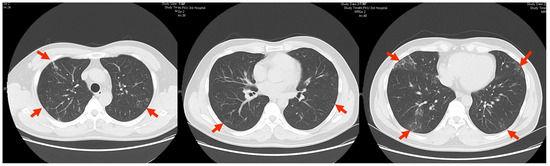

1. Case Presentation